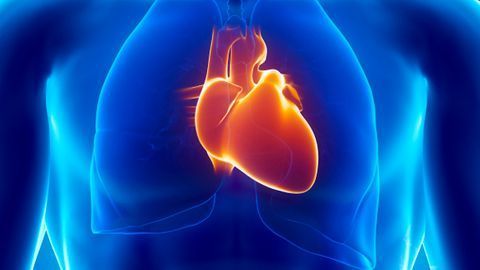

A new technology overcomes the challenges to cardiac imaging presented by spontaneous fetal movement.

Multi-modal approach maximizes imaging capabilities.